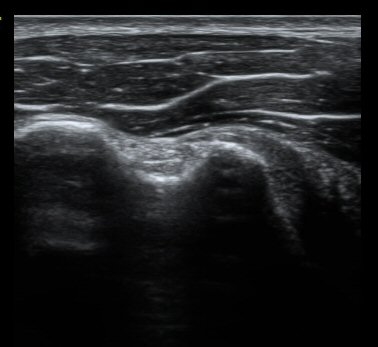

ȸÀü±Ù°³°£°Ý ³»Ãø Ⱦ´Ü¸é°Ë»ç¿¡¼­ °üÂûÇÑ °ß°©ÇÏ±Ù°Ç »óºÎ Á¾´Ü¸é°Ë»ç¿¡¼­ ¹Ì¼¼ÇÑ °£±ØÀÌ

°üÂûµÊ(±×¸² 3, 4). °ß°©ÇÏ±Ù°Ç È¾´Ü¸é°Ë»ç¿¡¼­µµ °ß°©Çϱٰdz» °£±ØÀÌ °üÂûµÊ(±×¸² 5).